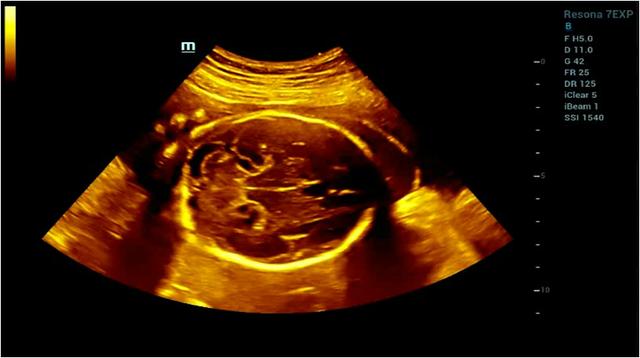

如何解决医生人手不足与孕产妇排长队的冲突?毋庸置疑,简单实用的智能超声系统就格外重要。在超声检查中,比如二维超声、多普勒超声、介入超声、三维超声,这些传统超声成像方法是通过“线扫描”技术成像,这意味着超声图像分辨率取决于发射频率。然而,随着发射频率增加到一定水平,分辨率很难再有显著提升。传统超声受空间分辨率、时间分辨力和组织均匀性三个参数的互相限制,若单提高一个则会牺牲其他及最终图像质量。所以传统超声形成的图像,朦胧,似真非真,依赖医生诊断经验,需要我们较长时间才能辩认,对诊断治疗出具检查结果带来较大难度。

而智能超声系统,就突破了传统超声波束合成在成像空间分辨力和时间分辨力的技术限制,扫描成像速度更快,提升了图像的时间帧频,减少了图像的运动伪像;提升了图像整体的均匀一致性,使我们不再需要为了图像的均匀性而频繁的调节焦点。而且通过图像智能算法判决,实现对于不同声速组织图像的最佳呈现,大大提高了图像呈现的速度和清晰度。

目前应用在临床领域的智能化超声,以国内的迈瑞智能化超声系统为代表,其图像清晰可见、一目了然,快速诊断,为医生和患者节省了时间,提升了诊治的效率,最大化提升了医生与医院的就诊效率。